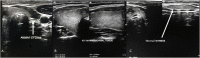

Case presentation: A 32-year-old Ugandan woman presented with a complaint of painless neck swelling of 3-months duration. The swelling was associated with a globus sensation. There was no history of thyroid - related problems or treatment prior to this presentation. Physical examination demonstrated a mobile right thyroid swelling without an obvious nodular contour. Neck ultrasound showed an absent left lobe of thyroid gland, a right lobe with a solitary nodule scoring two points on the Thyroid Imaging, Reporting and Data System (TI-RADS) and an isthmus in situ. Extensive search for possible ectopic thyroid tissue was negative. She was biochemically euthyroid. The patient was counseled about thyroid hemiagenesis and was put on a regular follow up in the clinic for the TI-RADS 2 nodule.